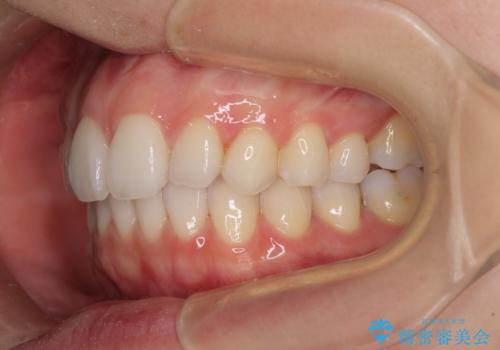

狭い上顎骨を拡大 急速拡大装置を併用したインビザライン矯正

- 前歯のクロスバイトや残存している乳歯を気にして来院された患者様です。

上顎骨の幅が下顎骨よりも小さいので、拡大装置により骨幅を広げて上下関係を改善し、その後インビザラインにて歯並びを整えることとしました。

上下の骨幅を改善したことで、スムーズに歯列矯正を行うことができました。